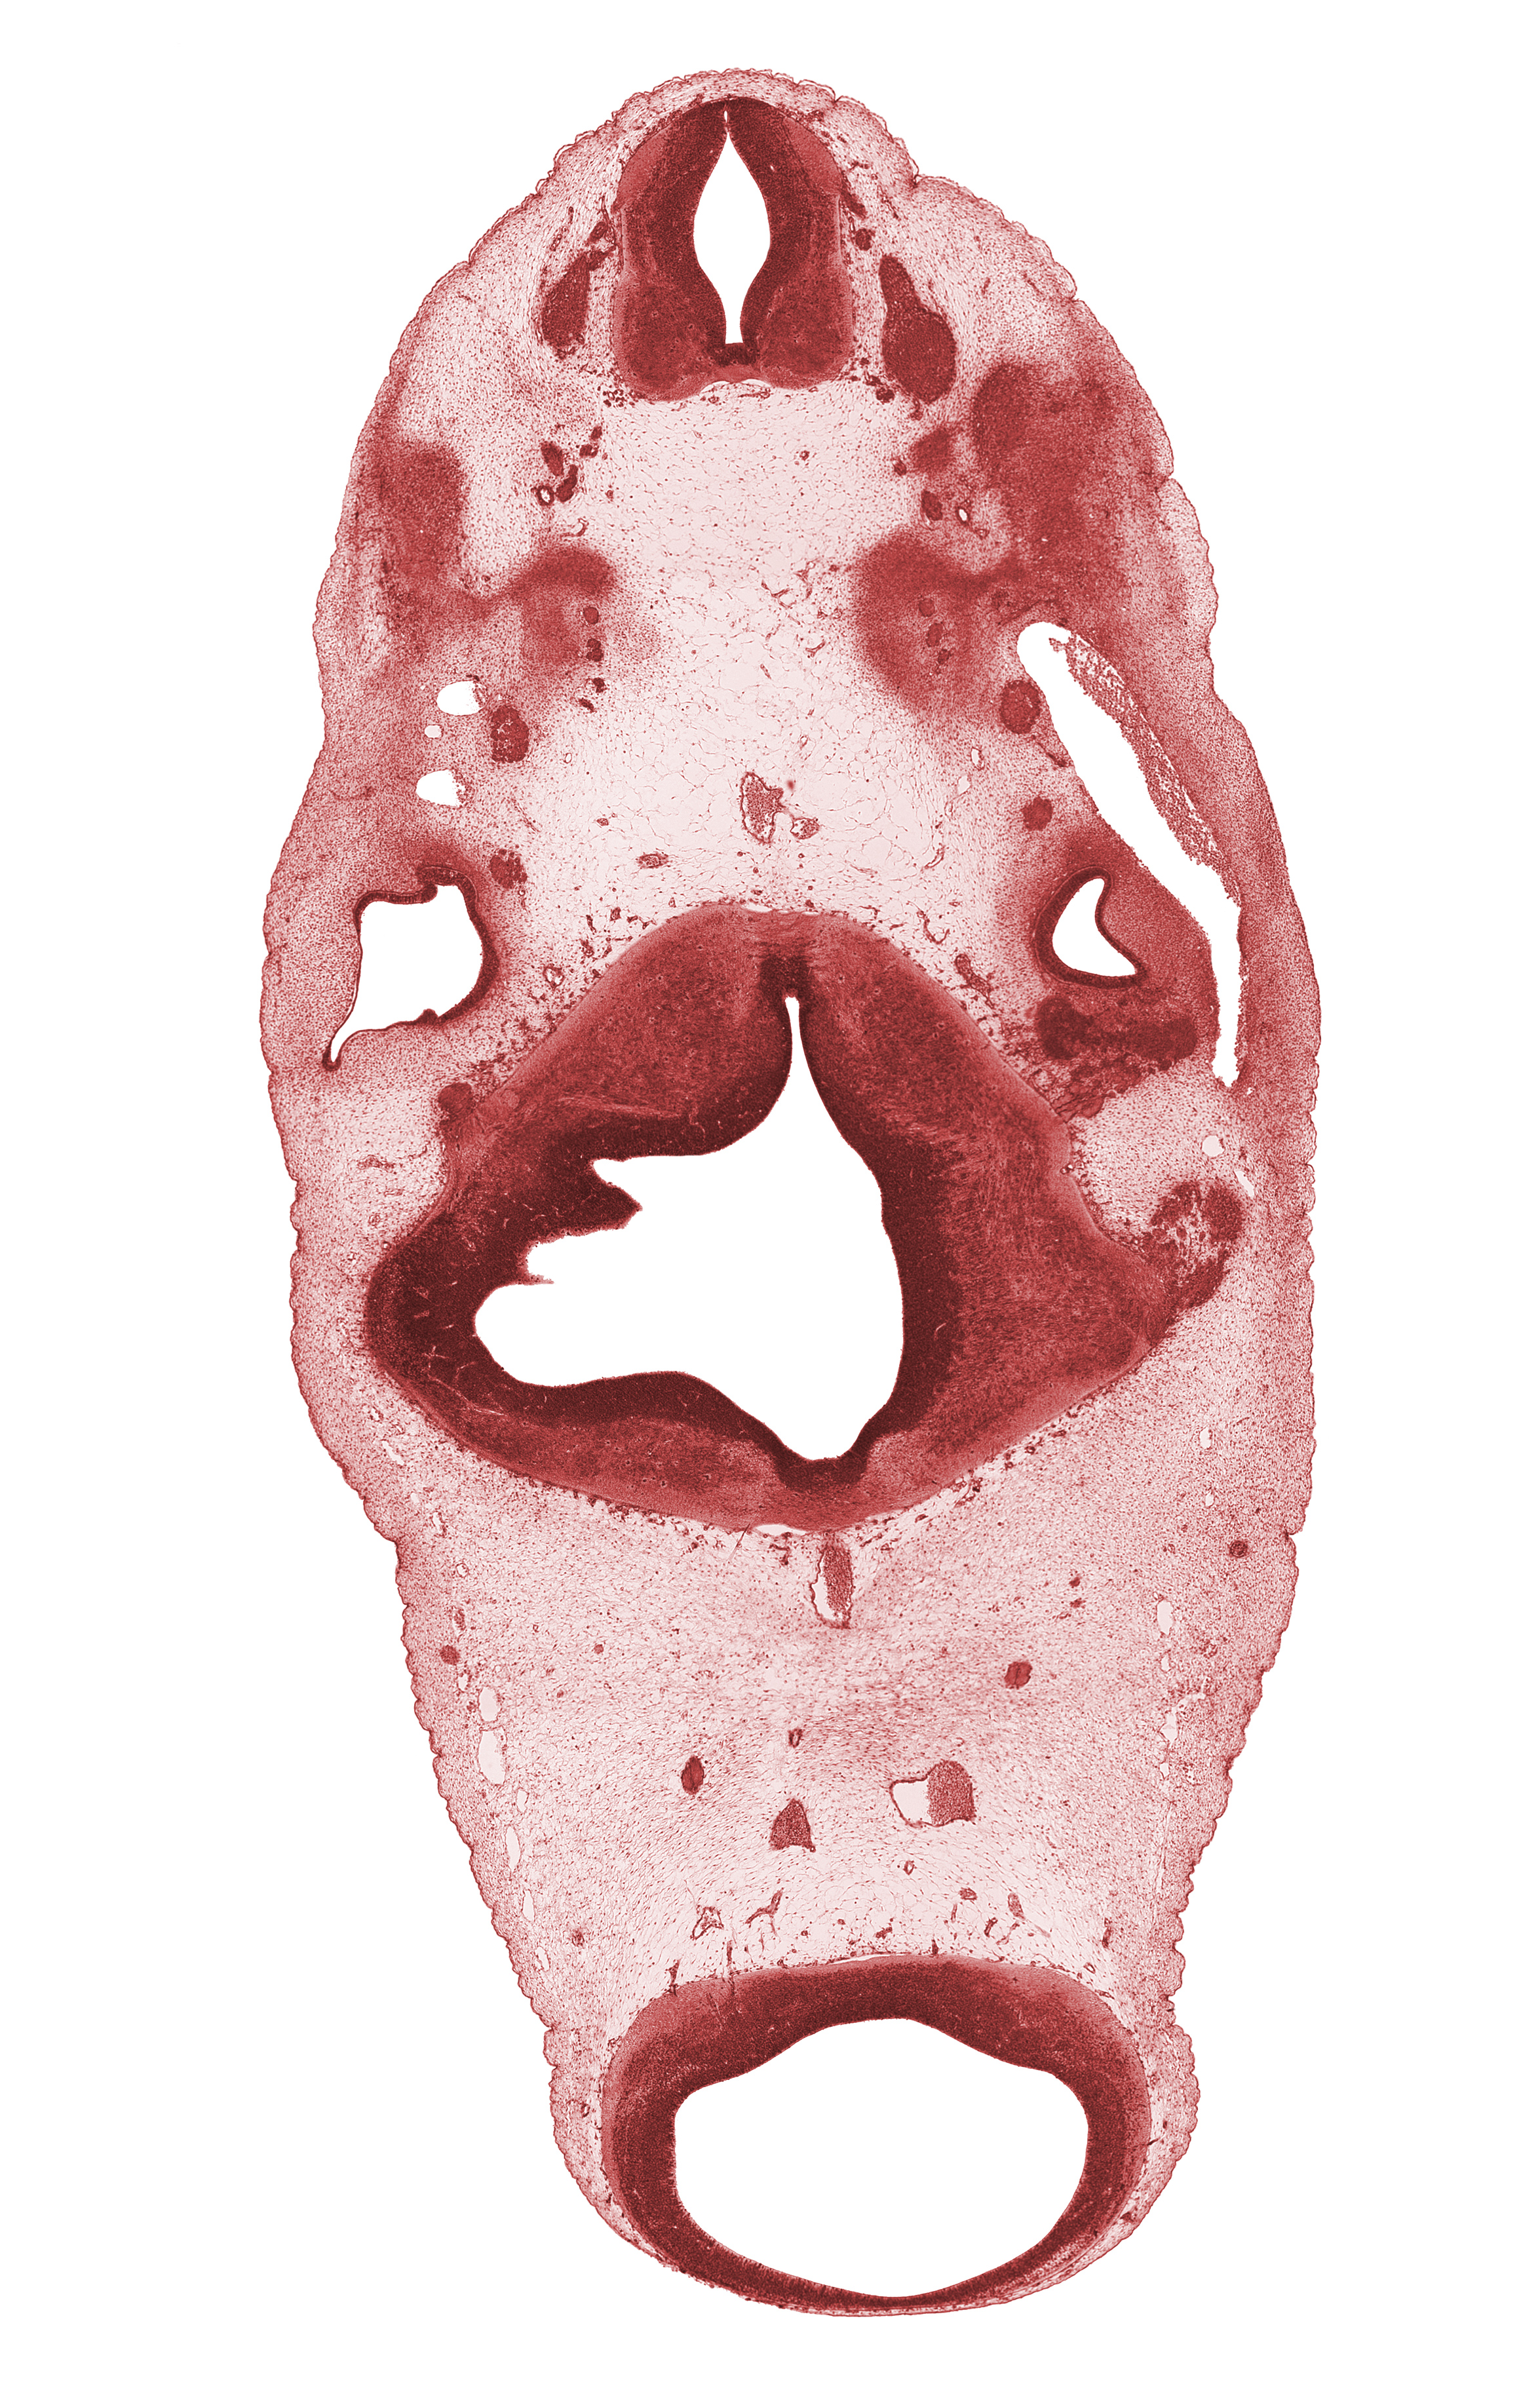

Carnegie Embryo #6520 | Location: 7-02-05

Keywords: C-2 spinal ganglion, C-2 ventral root, anterior semicircular duct, basal plate cartilage, basilar artery, edge of rhombomere 3, hypoglossal nerve (CN XII), lateral semicircular duct, posterior communicating artery, spinal accessory nerve (CN XI), trigeminal ganglion (CN V), vestibulocochlear ganglion (CN VIII)

Source: The Virtual Human Embryo.